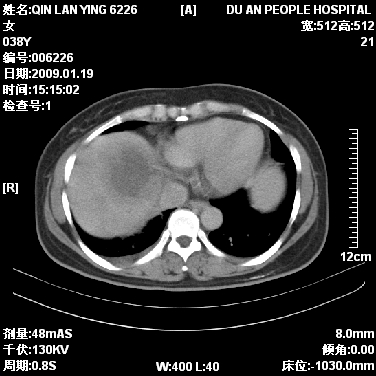

女,38岁,胸疼1个月。wbc:1万4

考虑----右肺中心型肺癌---阻塞性肺炎-----纵膈淋巴结及胸膜转移----肝脏转移

1)右肺中央型肺癌并右肺上叶阻塞性肺炎、节段性肺不张,纵隔淋巴结转移、右侧胸膜转移、肝脏转移。2)右侧胸腔少量积液。

1、右侧中央型肺癌并阻塞性肺不张,纵隔内、主动脉弓旁、右肺门淋巴结及肝脏转移可能性大,建议纤支镜进一步检查。

2、右侧胸腔积液。

本病例有几个容易诊断的地方:1、右肺上叶前段支气管闭塞,肺不张。2、淋巴结明显肿大。3、肝脏多个类圆形低密度影呈“牛眼征”改变,高度提示转移。

从影像学角度分析      右肺上叶中央型肺癌,并阻塞性不张、肺炎,纵隔淋巴结、膈顶淋巴结转移。

肝内两个大小不等低密度结节,内可见更低密度影,首先考虑肝内转移瘤,但联想到患者wbc1万4,建议楼主还是做个增强比较明确,除外肝脓肿的可能。